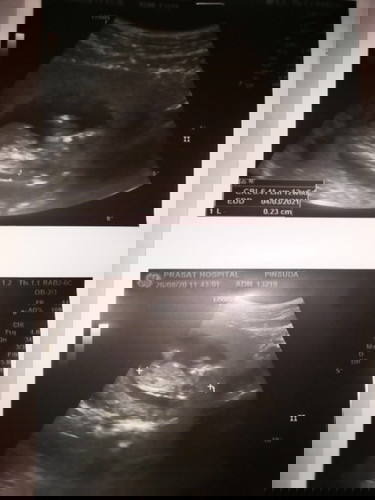

เเม่ๆๆรู้เพศลูกตอนกีวีคค่ะตอนนี้ท้องได้12+5wอยากทราบเพศลูกเเม่ๆช่วยดูหน่อยว่าเพศหญิงหรือชายค่ะ

ต้องดูรูปหว่างขาค่ะ ตอนนี้อาจจะยังอ่อนเกินไป ยังมองไม่ค่อยเห็นค่ะ แนะนำว่ารอสักหน่อย นัดรอบหน้าหมอซาวด์ก็น่าจะเห็นแล้วค่ะ ถ้าน้องให้ความร่วมมือ